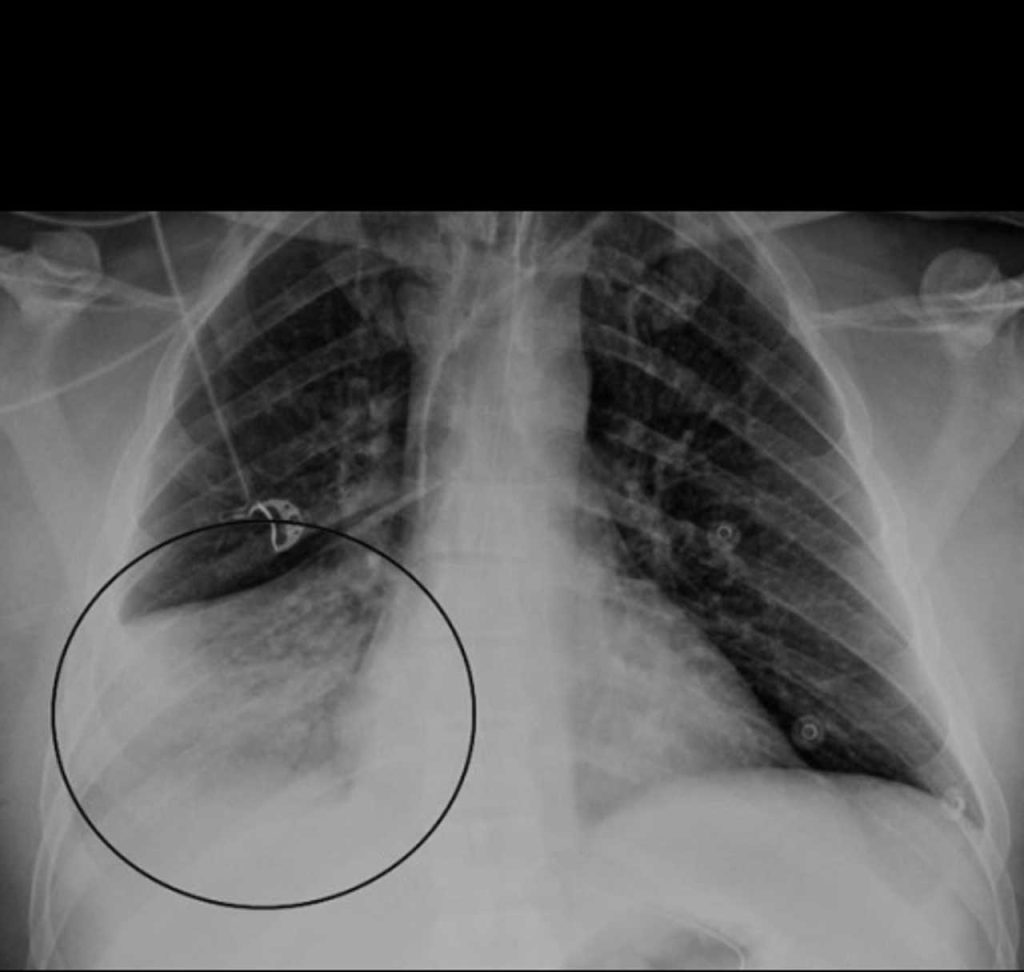

Virus Outbreak In China Sparking Concerns: Here’s What To Know About Hmpv

HMPV, a known virus, usually causes cold-like symptoms, including coughing, wheezing, a runny nose, and a sore throat. The new rise in cases, particularly among children under 14 in northern China, has officials urging caution as the Lunar New Year holiday approaches, a time when travel and gatherings often lead to spikes in illness. Data […]